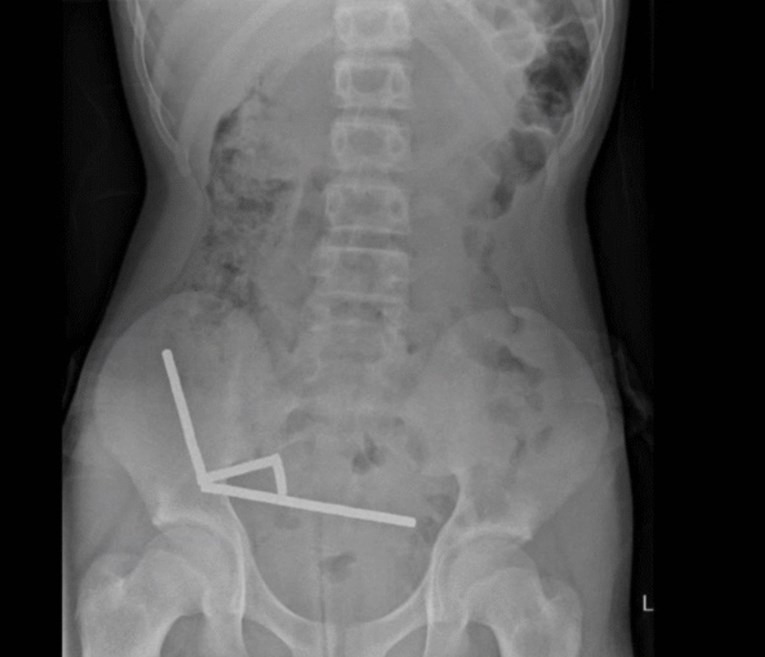

Rendgenske snimke otkrile su četiri lanca magneta raspoređena u različitim dijelovima dječakovih crijeva. Jednom kada su se našli u probavnom sustavu, mali metalni predmeti su se spojili. Tijekom operacije utvrđeno je da su se lanci magneta iz tankog crijeva i slijepog crijeva međusobno privukli, stišćući tkivo između sebe.

To je dovelo do prekida opskrbe krvlju i odumiranja nekoliko dijelova crijeva, stanja poznatog kao nekroza uslijed pritiska. Iako su kirurzi morali ukloniti dio crijeva, tinejdžer se uspješno oporavio i otpušten je kući osam dana kasnije.